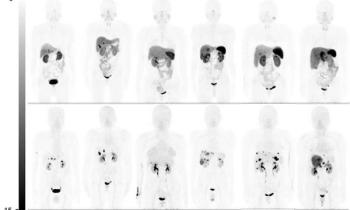

Patients who test negative with RT-PCR show lower levels of pulmonary consolidation on chest CT, indicating earlier disease.